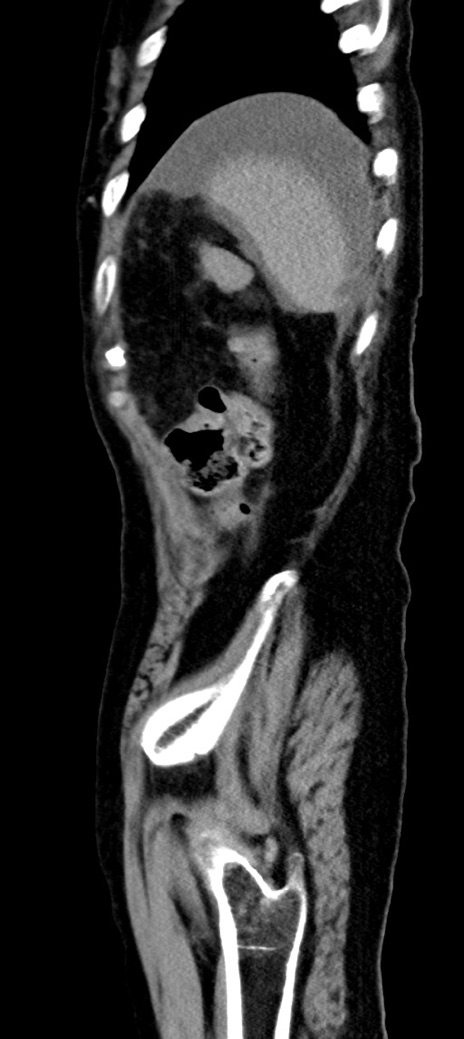

症例40(矢状断像)他院1日前

【症例】90歳代女性

【主訴】腹痛・嘔吐

【現病歴】 食欲低下、嘔吐があり昨日他院受診。肺炎と診断され入院となる。入院後より腹部全体に圧痛あり。胃管留置され経過みていたが、症状持続するため、

当院転院となる。

【既往歴】胸椎圧迫骨折、胆石症

【身体所見】腹部:中央に激痛あり、圧痛あり、反跳痛不明

【データ】WBC 17100、CRP 18.82